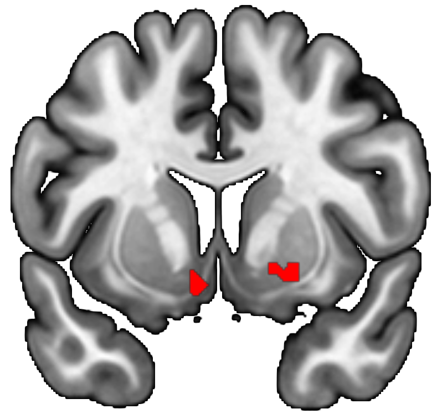

Fatigue is increasingly recognized as a behaviorally multifaceted construct, encompassing at least three interacting dimensions: (1) feelings of tiredness, reflecting interoceptive and emotional appraisal of bodily state; (2) effort perception, which arises from the integration of sensory and motor signals to estimate exertion; and (3) effort cost, the subjective valuation of physical effort during decision-making. The multifaceted nature of fatigue suggests a distributed neural architecture. Feelings of tiredness can be associated with interoceptive and salience-related regions; effort perception with sensorimotor integration hubs; and effort cost with valuation and motivation circuits. This project will develop objective markers that quantify fatigue in real time and reveal the behavioral and neural mechanisms that give rise to it.